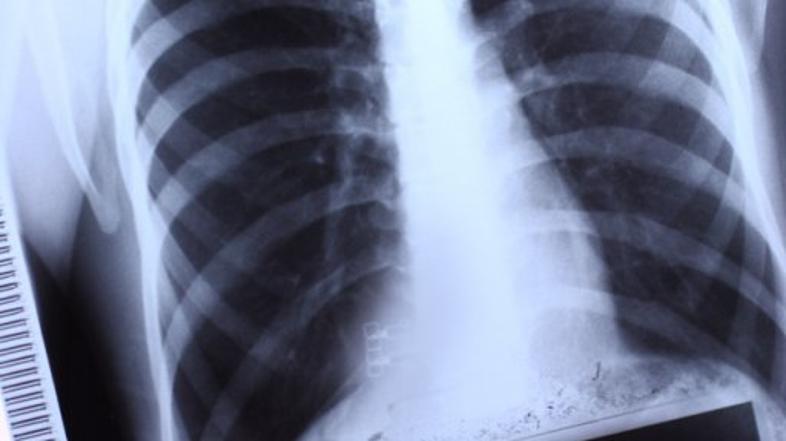

Pljuča Shutterstock

Umrli za koronavirusom so imeli nepopravljive poškodbe pljuč so razkrili zdravniki iz univerzitetne klinike v nemškem Augsburgu, ki so sodelovali pri obdukcijah umrlih zaradi novega koronavirusa. Odkrili so, da so imeli ti "nenavadno težke in domnevno nepopravljive poškodbe pljuč", je v petek poročala nemška tiskovna agencija dpa.

Prepričani so, da do poškodb pljuč ni prišlo zaradi umetnega predihavanja pacientov, ampak najverjetneje neposredno zaradi covida-19. Kot so zapisali v univerzitetni kliniki, so zdravniki mnenja, da so prav te poškodbe razlog za smrt pacientov.

Ekipa v Augsburgu je opravila obdukcije 19 umrlih zaradi novega koronavirusa in svoje izsledke objavila v reviji Journal of the American Medical Association. V povprečju so bile obducirane žrtve novega koronavirusa stare 79 let. Prav vsi so imeli že pred okužbo hude bolezni, ki pa niso bile neposredni razlog za smrt, direktorja patologije v Augsburgu povzema dpa. Agencija dodaja, da zdravniki pri obdukciji na preostalih organih umrlih niso odkrili vidnih sprememb.